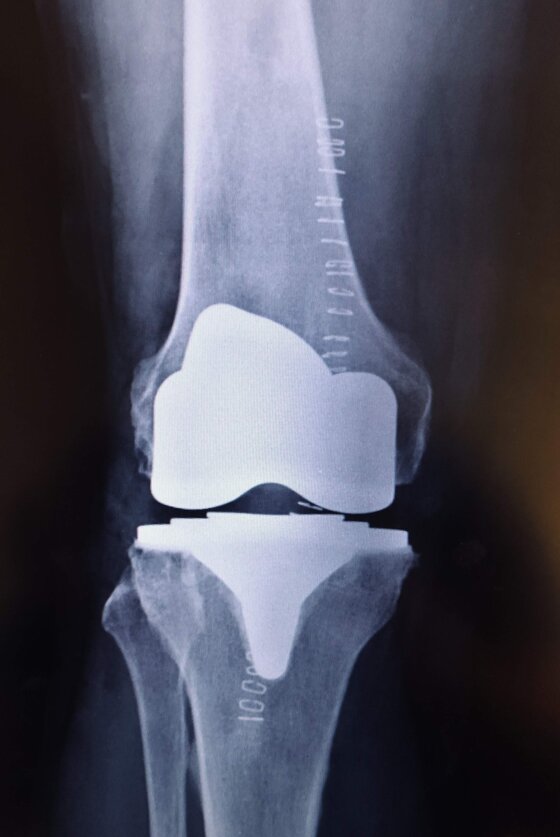

Radiografie post-operatorie in AP e LL di intervento chirurgico di artroprotesi cementata di ginocchio in pz donna con sovrappeso. In questo caso è stata utilizzata una protesi postero-stabilizzata (PS) con sacrificio quindi del legamento crociato posteriore (LCP)